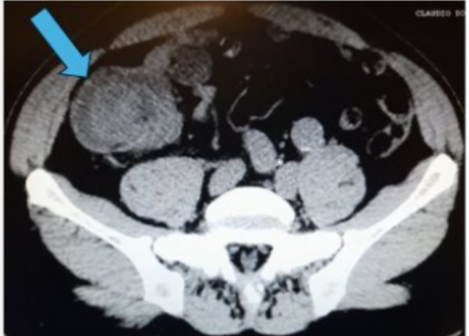

Male patient, 62 years old, overweight, hypertensive and regularly using antihypertensive medication, admitted to the digestive system surgery service at Hospital da Cidade-Salvador- Bahia- Brazil, with clinical symptoms of abdominal pain in the hypogastrium, radiating to the right iliac fossa. Report of abrupt onset, with strong intensity and no improvement after analgesia. Pacient reports passing gas and feces. On physical examination, the abdomen was globular due to a fatty panniculus, without abdominal distension, tympanic, painless on superficial and deep palpation. Surgical history: conventional appendectomy, 10 years ago. Computed tomography of the total abdomen showed a point of mechanical obstruction at the level of the distal ileum and cecum, with classic radiological signs of intestinal intussusception: pseudokidney sign (Figure 1) and target sign (Figure 2). In a multidisciplinary discussion with the radiolo team specialized in the digestive system, radiological characteristics of benign lipomatous neoplasia were highlighted: Lesion measuring 4.8 x 3.0 cm, associated with well-defined margins, rounded and with a fat density similar to that of mescolon, without prominent peri-colonic lymph node (Figure 3). The patient's clinical condition worsened due to abdominal distension and post-food vomiting, undergoing surgical treatment with resection of the distal ileum and cecum and primary anastomosis. No need for wide colectomy or retroperitoneal lymphadenectomy. The patient was discharged from hospital on the 5th postoperative day without abdominal pain, with a bland oral diet and normal intestinal rhythm. Pathological anatomy showed a benign lipomatous lesion measuring (4.5 x1.5 cm) in the ileum.

Figure 2. Ileo-colonic intussusception.Target sign (blue arrow).